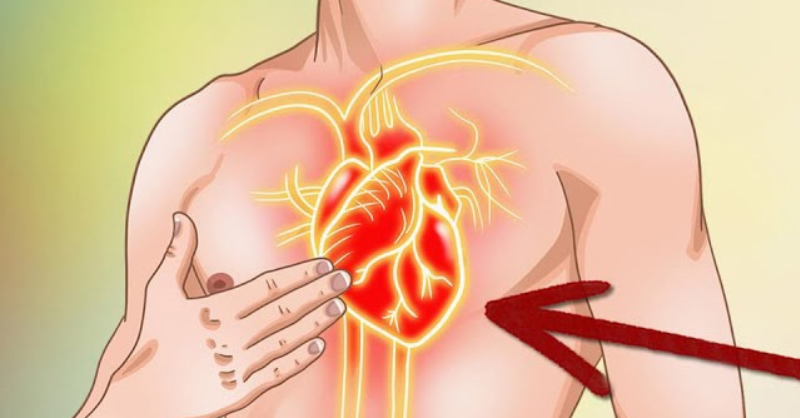

In the event of a heart at.tack, you only have seconds to save your life. What should you do?

When it comes to a heart attack, time is critical. While these situations may not be common, knowing how to respond can truly make a difference. And beyond...